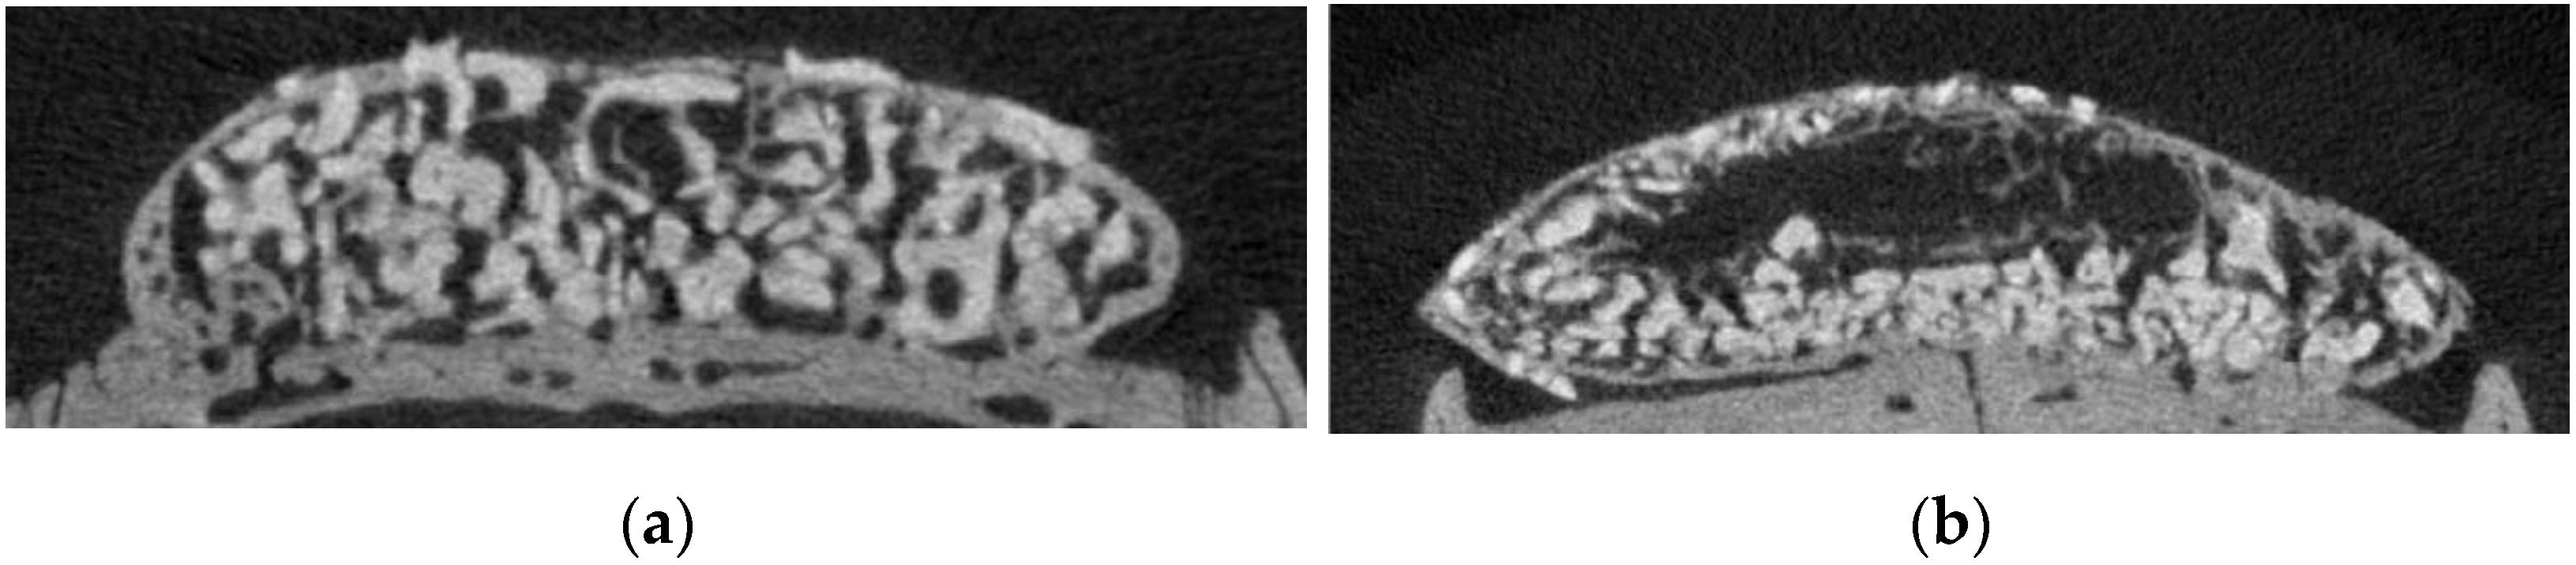

3.1. μ-CT Analysis of BV, BMD, TbTh, and TbSp